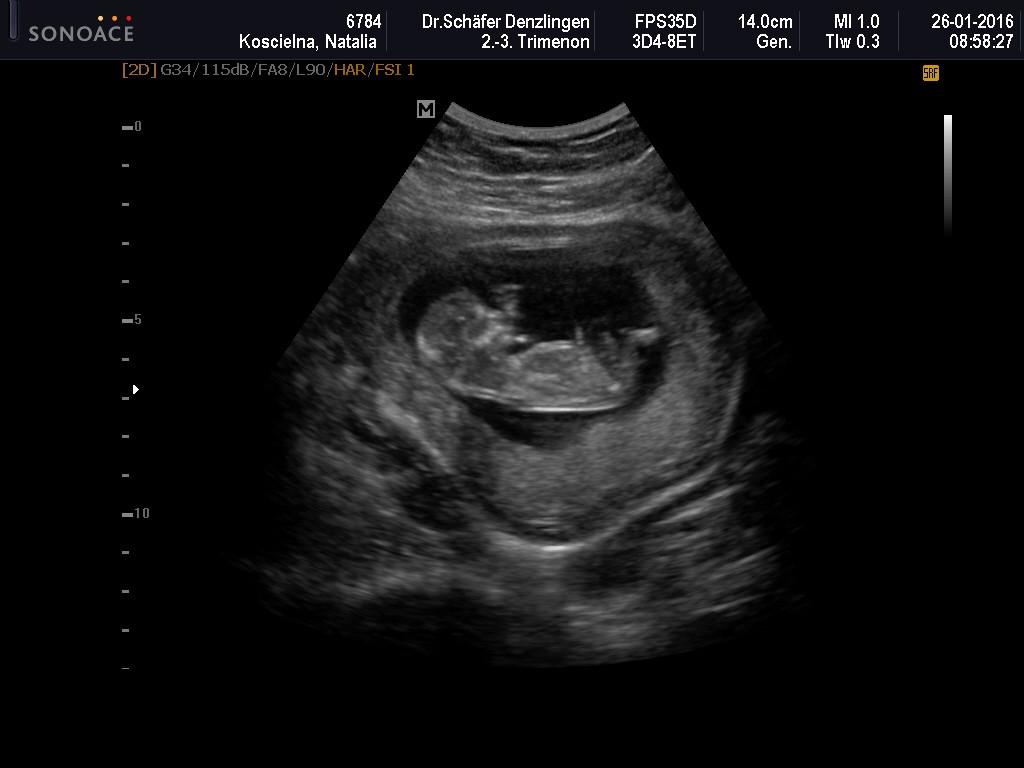

Wczoraj miałam wizytę - wszystko ok, ciąża troszkę większa, bo wszytskie pomiary pokazywały na 12+4, wszystko ok, więc ulga wielka, bardzo długo mi robił usg, mierzył i wszystko ok. Kolejne badania do zrobienia na tokspolazmoze a już sama chciałam sobie robić. Kolejna wizyta za 3 tygodnie. pokazuje zdjęcie z usg, po lewejrączka przy główce, na drugim nóżki i brzuszek![]()

dał mi zdjęcie i mówi :ma Pani swoje nóżki i rączki